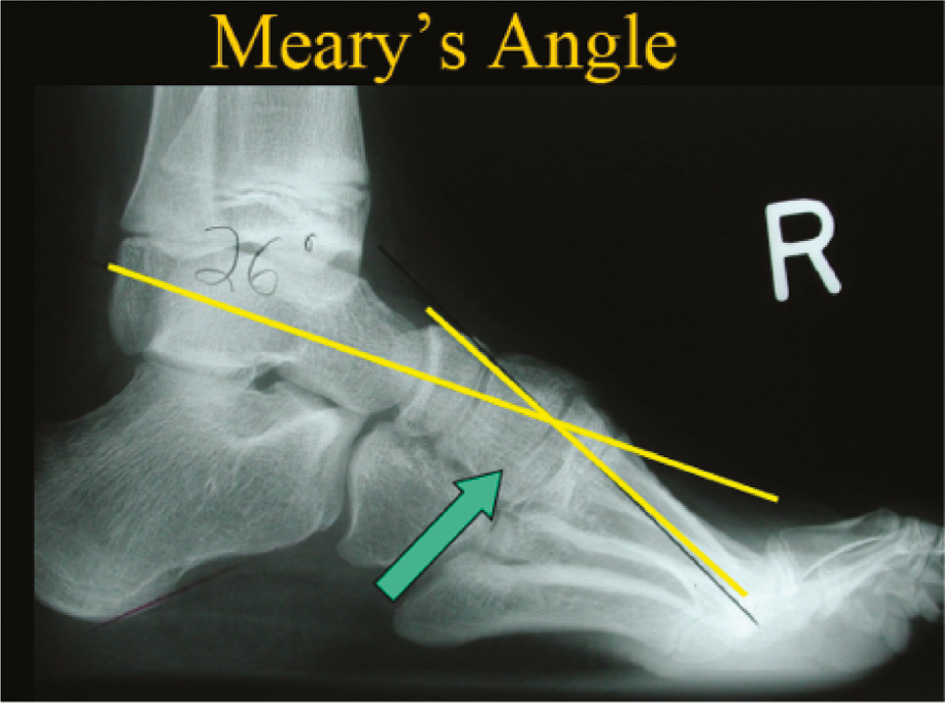

Radiographic evaluation of pes cavus is typically done with standing anteroposterior (AP) and lateral radiographs of the ankle as well as standing AP, lateral, and oblique radiographs of the foot. On the AP foot view, the talocalcaneal angle may be drawn to indicate the degree of hindfoot varus present. A talocalcaneal angle less than 20 to 25 degrees would be considered pathologic, with the normal range between 25 to 45 degrees (Figure 9). The talonavicular angle may additionally be drawn to assess the degree of forefoot adduction, with a value greater than 7 degrees indicating pathology. There may also be metatarsal overlap seen on this image that would indicate pronation of the forefoot. On the lateral foot view, Meary’s angle (lateral talo-first metatarsal angle) may be drawn. A break in this line is caused by plantarflexion of the first ray and a value more than 4 degrees apex dorsal indicates cavus (Figure 10). In the calcaneocavus foot with hindfoot dorsiflexion, the calcaneal pitch (or calcaneal inclination) is typically over 30 degrees (Figure 11).

Figure 10. Cavus is noted radiographically if the talus-1st metatarsal angle is greater than 5 degrees.

jposna20220035_fig10.jpg

Other midfoot osteotomies have been used less frequently with good outcomes in a forefoot driven cavus, including the Japas osteotomy.45 The Japas osteotomy is a dorsal closing wedge osteotomy through the entire midfoot with the apex at the navicular and extending medially and laterally to end just proximal to the first and fifth tarsometatarsal joints. Meary also proposed a wedge tarsectomy which involved a closing wedge osteotomy through the navicular, cuboid and cuneiform bones, which is another variant of the multiple described midfoot osteotomies.46 Some authors choose to simply utilize a wedge osteotomy at the medial cuneiform and cuboid bones, addressing the medial and lateral borders of the foot while avoiding an osteotomy traversing the entire midfoot.47,48 This may not be as powerful in correcting forefoot pronation, but it may present less morbidity and postoperative stiffness when compared to osteotomies through the entire midfoot.24 Faldini reported good to excellent outcomes in 92% of patients (n=24 feet) with flexible hindfoot varus following a combination of plantar fasciotomy, osteotomy through the cuboid and naviculocuneiform joint, Jones extensor hallucis longus transfer, and dorsiflexion osteotomy of the first metatarsal.47 Mean calcaneal pitch improved by an average of 10 degrees, and the mean Meary angle improved substantially from 25 degrees to 2 degrees postoperatively. Even when performing separate wedge resections of the cuboid and naviculocuneiform joint, radiographic correction at the apex of the deformity in the midtarsal region was achieved while midfoot motion was preserved.47

With the myriad of osteotomies available, especially through the midfoot region, it is critical that the surgeon determine where the apex of the cavus deformity is centered in the sagittal plane (Figure 16). Each patient requires a personalized approach to address forefoot equinus. Tarsal osteotomies should be selected if the apex of the cavus deformity lies about the midfoot region. If the deformity is centered closer to the first metatarsal, then a dorsiflexion first metatarsal osteotomy, typically in combination with plantar fascia release and peroneus longus transfer, is indicated. Additionally, one study has suggested that dorsal hemiepiphysiodesis of the first metatarsal along with plantar fascia release in skeletally immature patients (n=24 feet, age 7-13 years) may be another option to address forefoot equinus centered at the first metatarsal. The authors demonstrated good clinical outcomes and correction of hindfoot varus as well as significant improvements in radiographic parameters including Meary’s angle, with full correction achieved in younger patients by skeletal maturity.49